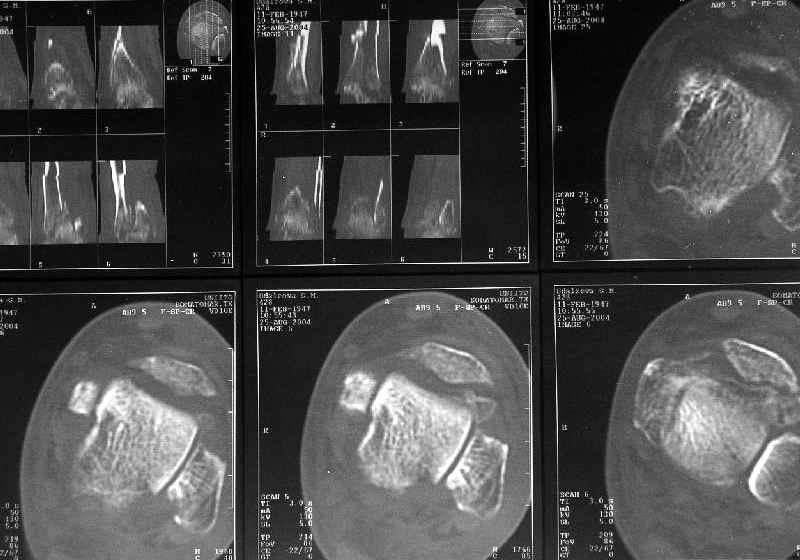

Дама 56 лет 6 недель назад получила спиральные переломы дистальных отделов костей голени. По месту жительства наложили гипс.

Сейчас вот, получается, спохватились. Снимки и КТ в приложении. Какой вариант тут предпочтительнее - открытая мобилизация, репозиция и внутренняя или наружная фиксация? Или ограничиться только резекцией костного шипа над шейкой тарана?Заранее спасибо.A female 56 y.o. 6 weeks ago sustained a fracture of the distal tibia/fibula. At the initial hospital a plaster cast was applied. Now she was referred to our unit. At the moment there is no pain, no obvious mobility. Images and CT attached.What is the best option here? Mobilize the fracture, perform open reduction and internal or external fixation? Or just to cut the anterior spike over the talar neck? THX in advance.

Здесь повреждение не диафизарное, смотрели состояние суставного конца кости и взаимоотношения таранной кости с этим шипом. Результаты КТ как раз повлияли на план, без нее пошли бы латеральным доступом, а после - передне-медиальным.